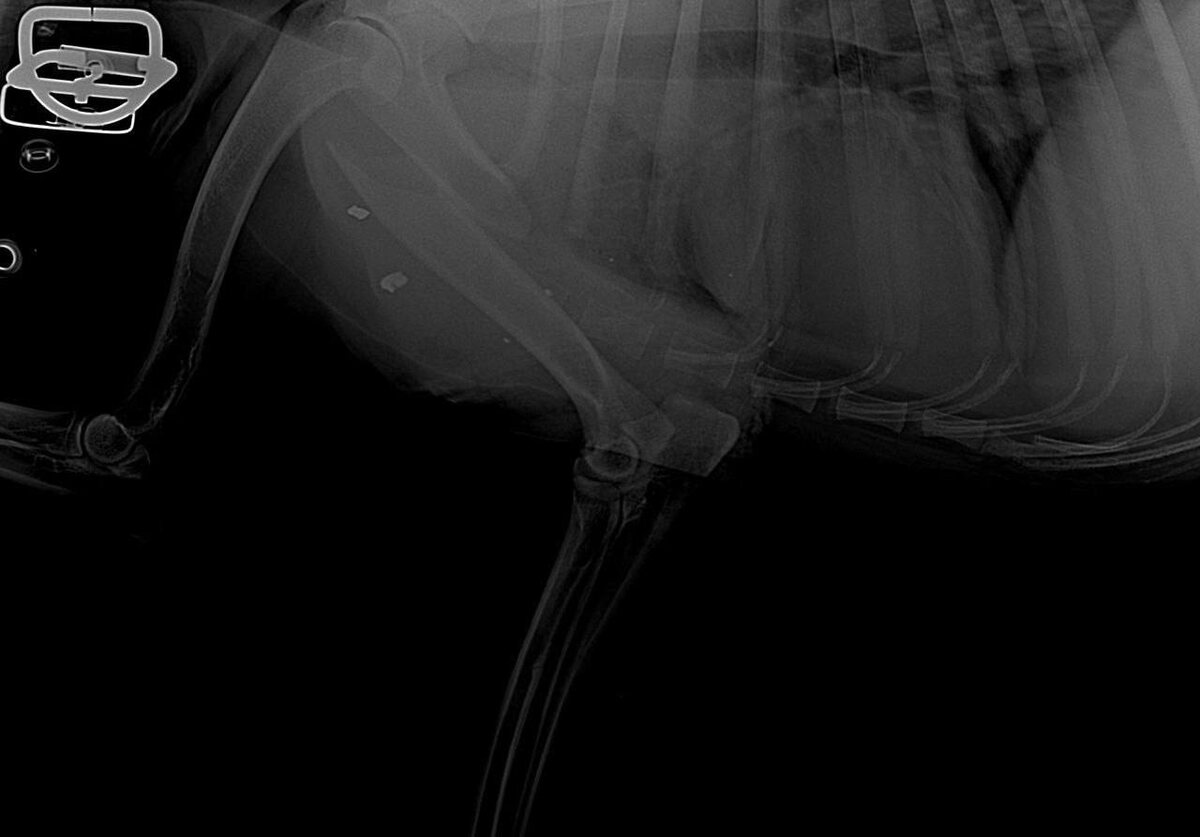

Но самое тяжёлое — серьезно пострадала одна из собак. Сейчас она в клинике. Завтра ей предстоит сложная операция: перелом со смещением, потребуется пластина и фиксатор. Стоимость лечения — около 30 000 рублей, которых у приюта, как всегда, нет.